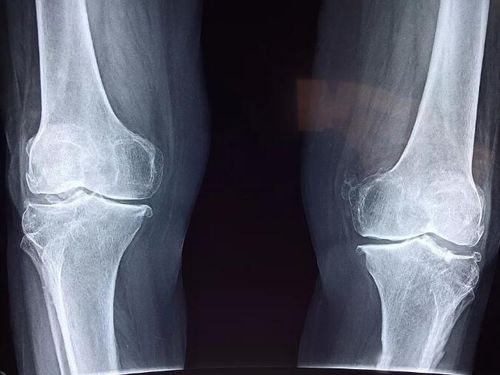

正常膝关节,正常膝关节正位片图片

如图所示,正常膝关节的关节软骨光滑有弹性.

正常膝关节正位片图片

正常膝关节x线图片

正常膝关节x片

正常膝关节x光片